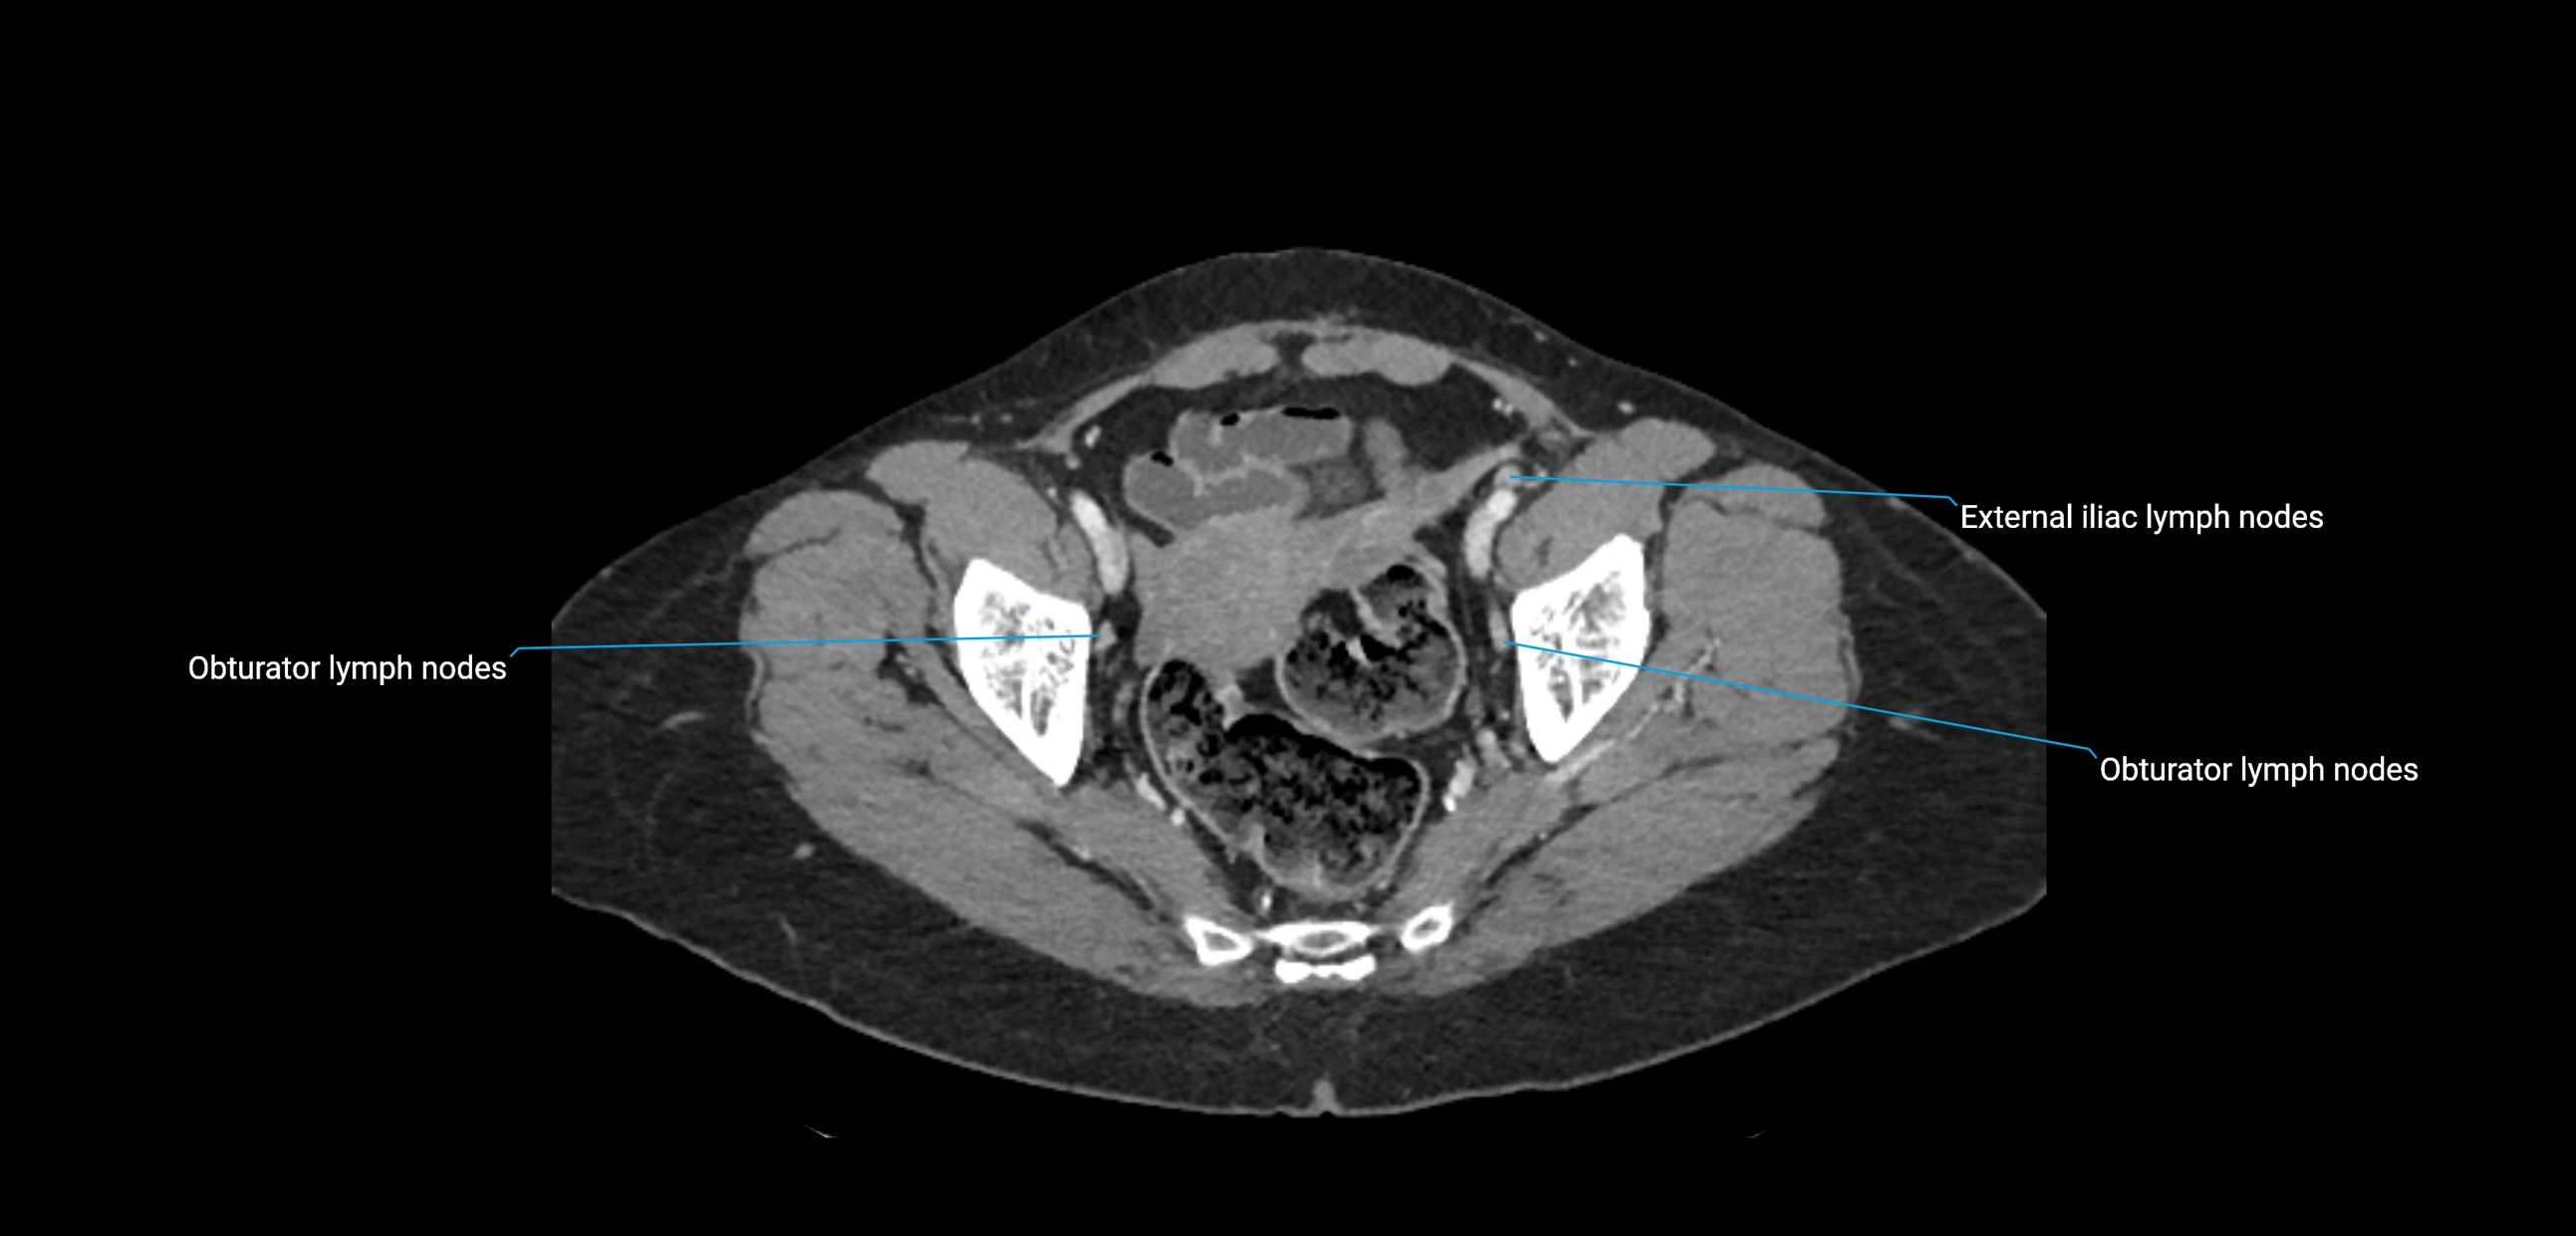

CT Appearance

CT Pre-Contrast:

• Nodes appear as soft-tissue density nodules adjacent to the aorta and IVC

• Calcification may be seen in chronic infections (e.g., tuberculosis)

CT Post-Contrast:

• Normal nodes enhance homogeneously

• Malignant nodes may show heterogeneous enhancement, central necrosis, or conglomerate formation

• Size >1 cm short axis is suspicious, though morphology and distribution are equally important